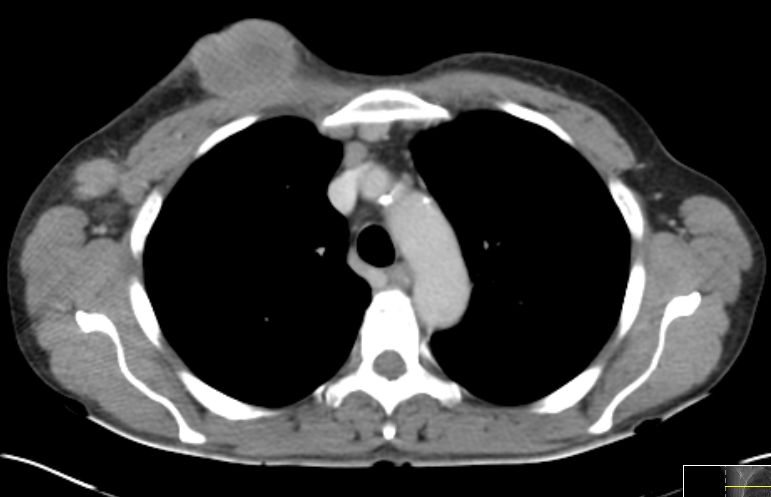

Mammographie,

MRT,

Sonographie,

Thermographie,

Szintigraphie,